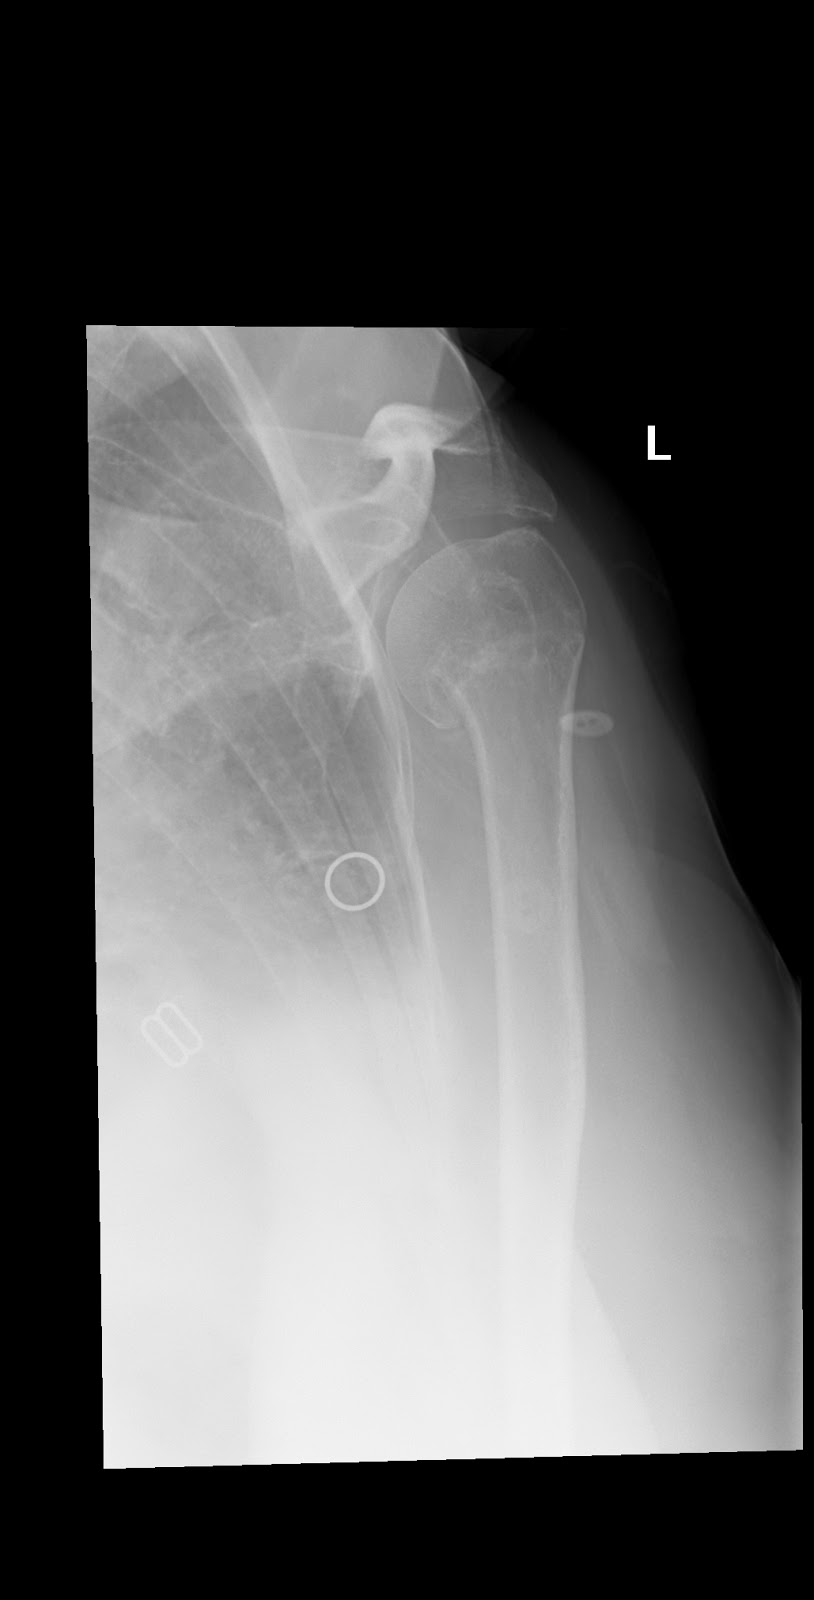

Posterior Shoulder Dislocation EMbeds.co.uk Shoulder Subluxation No Pain Describe the diagnostic approach for evaluating shoulder subluxation injuries. shoulder subluxation, a subset of shoulder instability, occurs when the shoulder joint partially dislocates. a shoulder subluxation is a partial shoulder dislocation involving the ball of the upper arm bone (the humerus). It is more annoying, preventing. shoulder subluxation can cause pain and weakness in the shoulder and. Shoulder Subluxation No Pain.

Cureus Recurrent Shoulder Posteroinferior Subluxation Status Post Shoulder Subluxation No Pain shoulder subluxation happens when the ball of the upper arm bone comes partly out of its socket. In this condition the humeral head slips out of the glenoid cavity as a result of weakness of rotator cuff or looseness of the glenohumeral ligaments. What is shoulder subluxation and how is it treated? a shoulder subluxation is a partial. Shoulder Subluxation No Pain.

Shoulder dislocation anterior Image Shoulder Subluxation No Pain a shoulder subluxation is a partial shoulder dislocation involving the ball of the upper arm bone (the humerus). In this condition the humeral head slips out of the glenoid cavity as a result of weakness of rotator cuff or looseness of the glenohumeral ligaments. What is shoulder subluxation and how is it treated? Describe the diagnostic approach for evaluating. Shoulder Subluxation No Pain.